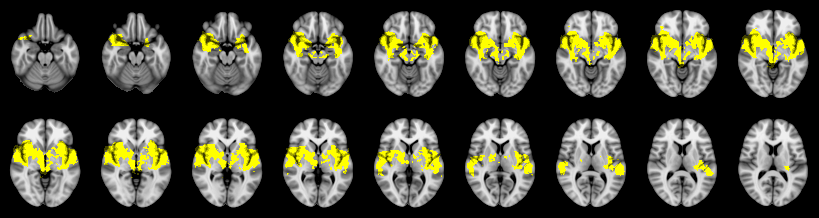

Not combined

Face:

Hand:

Foot: